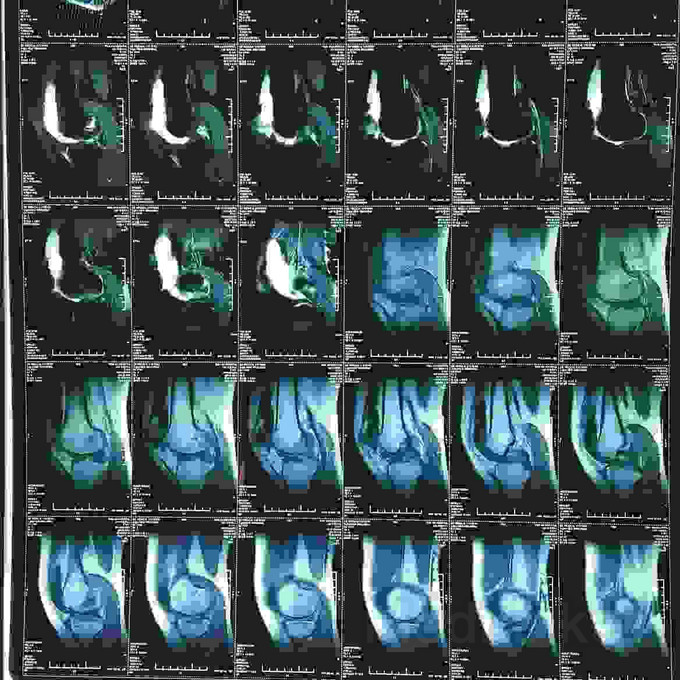

髌骨脱位的治疗?

髌骨脱位

患者女,19岁,双膝关节习惯性髌骨脱位10余年,多家医院建议手术治疗,2个月前摔伤致左髌骨脱位,于某院行手术治疗,经家人商讨后决定再行右膝手术治疗来我院。请老师们指点是否需要调整髌骨远端力线?做何手术最为简单有效?具体是做单纯外侧支持带松解?外侧支持带松解+内侧关节囊缩紧筋膜成形?外侧支持带松解+髌腱手术?外侧支持带松解+胫骨结节内移?还是外侧松解+内侧紧缩成形+胫骨结节内移?还是什么?